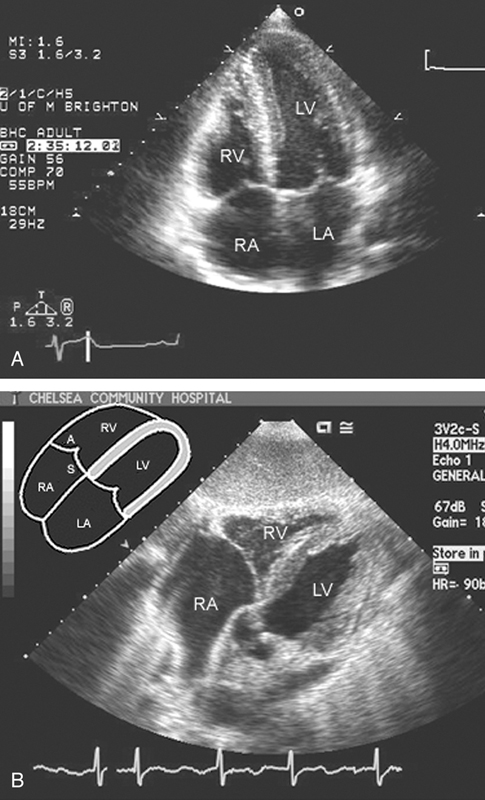

فحوصات تشخيصية لبعض امراض القلب والشرايين التاجية